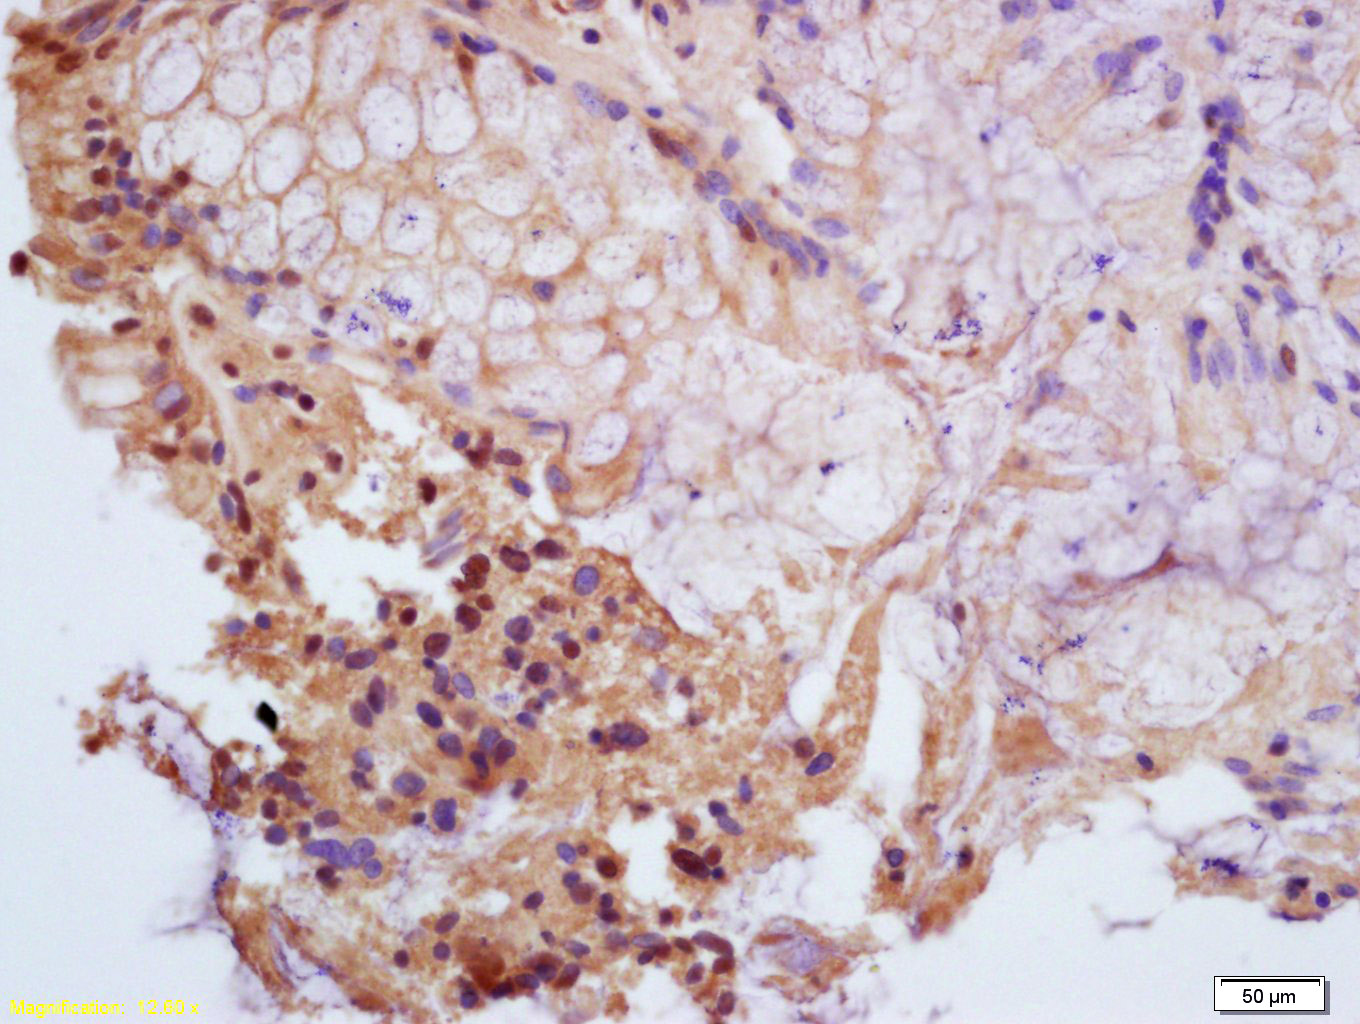

Tissue/cell: human gastric carcinoma; 4% Paraformaldehyde-fixed and paraffin-embedded; Antigen retrieval: citrate buffer ( 0.01M, pH 6.0 ), Boiling bathing for 15min; Block endogenous peroxidase by 3% Hydrogen peroxide for 30min; Blocking buffer (normal goat serum,C-0005) at 37鈩? for 20 min; Incubation: Anti-Phospho-PPAR Gamma(ser112) Polyclonal Antibody, Unconjugated(bs-3737R) 1:200, overnight at 4擄C, followed by conjugation to the secondary antibody(SP-0023) and DAB(C-0010) staining

Tissue/cell: human colon carcinoma; 4% Paraformaldehyde-fixed and paraffin-embedded; Antigen retrieval: citrate buffer ( 0.01M, pH 6.0 ), Boiling bathing for 15min; Block endogenous peroxidase by 3% Hydrogen peroxide for 30min; Blocking buffer (normal goat serum,C-0005) at 37鈩? for 20 min; Incubation: Anti-Phospho-PPAR Gamma(ser112) Polyclonal Antibody, Unconjugated(bs-3737R) 1:200, overnight at 4擄C, followed by conjugation to the secondary antibody(SP-0023) and DAB(C-0010) staining